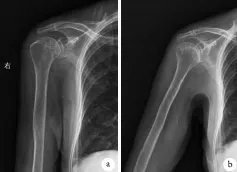

文章插图

术后X片未见钙化灶